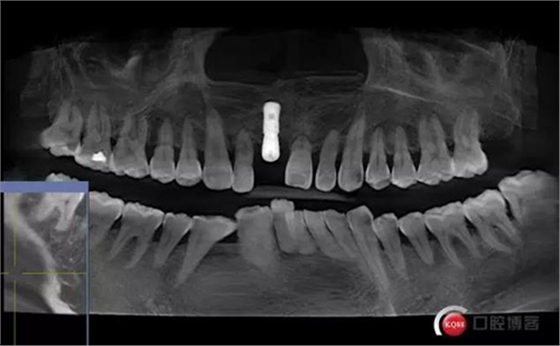

患者:王XX 年齡:42 上前牙松動(dòng)數(shù)年,從未做過任何處理,今來院就診;檢查:CBCT示上前牙區(qū)顎側(cè)一大小約7x7mm囊腫;治療計(jì)劃:即刻種植同期摘除囊腫

術(shù)前CBCT

術(shù)后CBCT